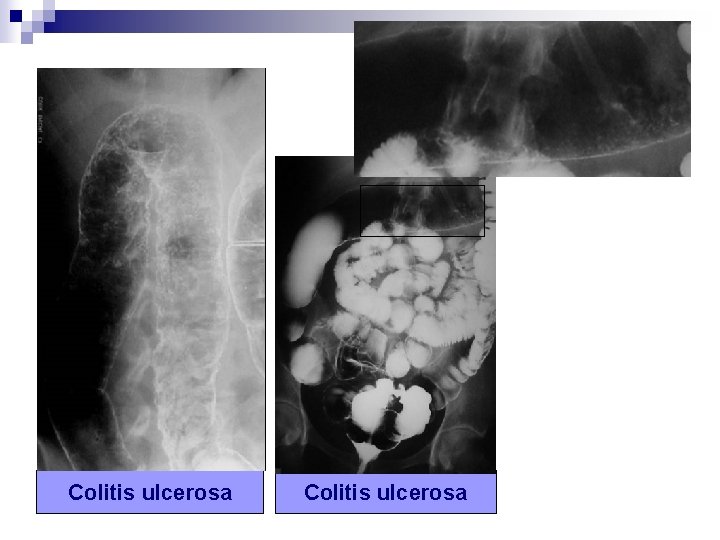

1) Patrón granular n n n Ligeras elevaciones de la superficie mucosa, poco perceptibles y de bordes poco nítidos. Se ven como pequeñas radiolucencias en el pool de bario. Es como “rociar un plato con sal” Implica mucosa elevada por edema, exudado inflamatorio o tumor. Ejemplos: RGE, colitis ulcerosa, enf. Crohn… XXIX Congreso Nacional de la SERAM. Sevilla 23, 24, 25 y 26 Mayo 2008

Colitis ulcerosa

Colitis ulcerosa XXIX Congreso Nacional de la SERAM. Sevilla 23, 24, 25 y 26 Mayo 2008